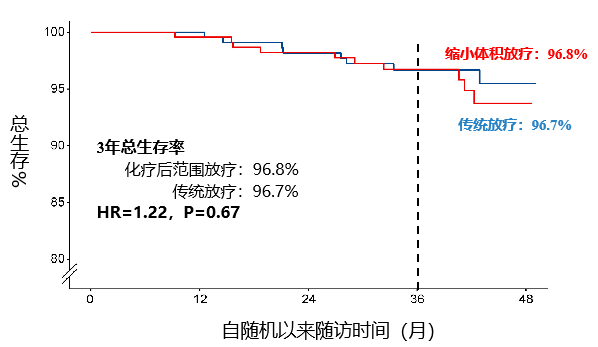

研究结果表明,与化疗前肿瘤范围放疗组相比,化疗后治疗范围放疗组局部区域无复发生存率实现非劣效目标(非劣效P=0.004)、总生存率也没有无差异(P=0.067)。

3年总生存率:96.8% vs. 96.7%